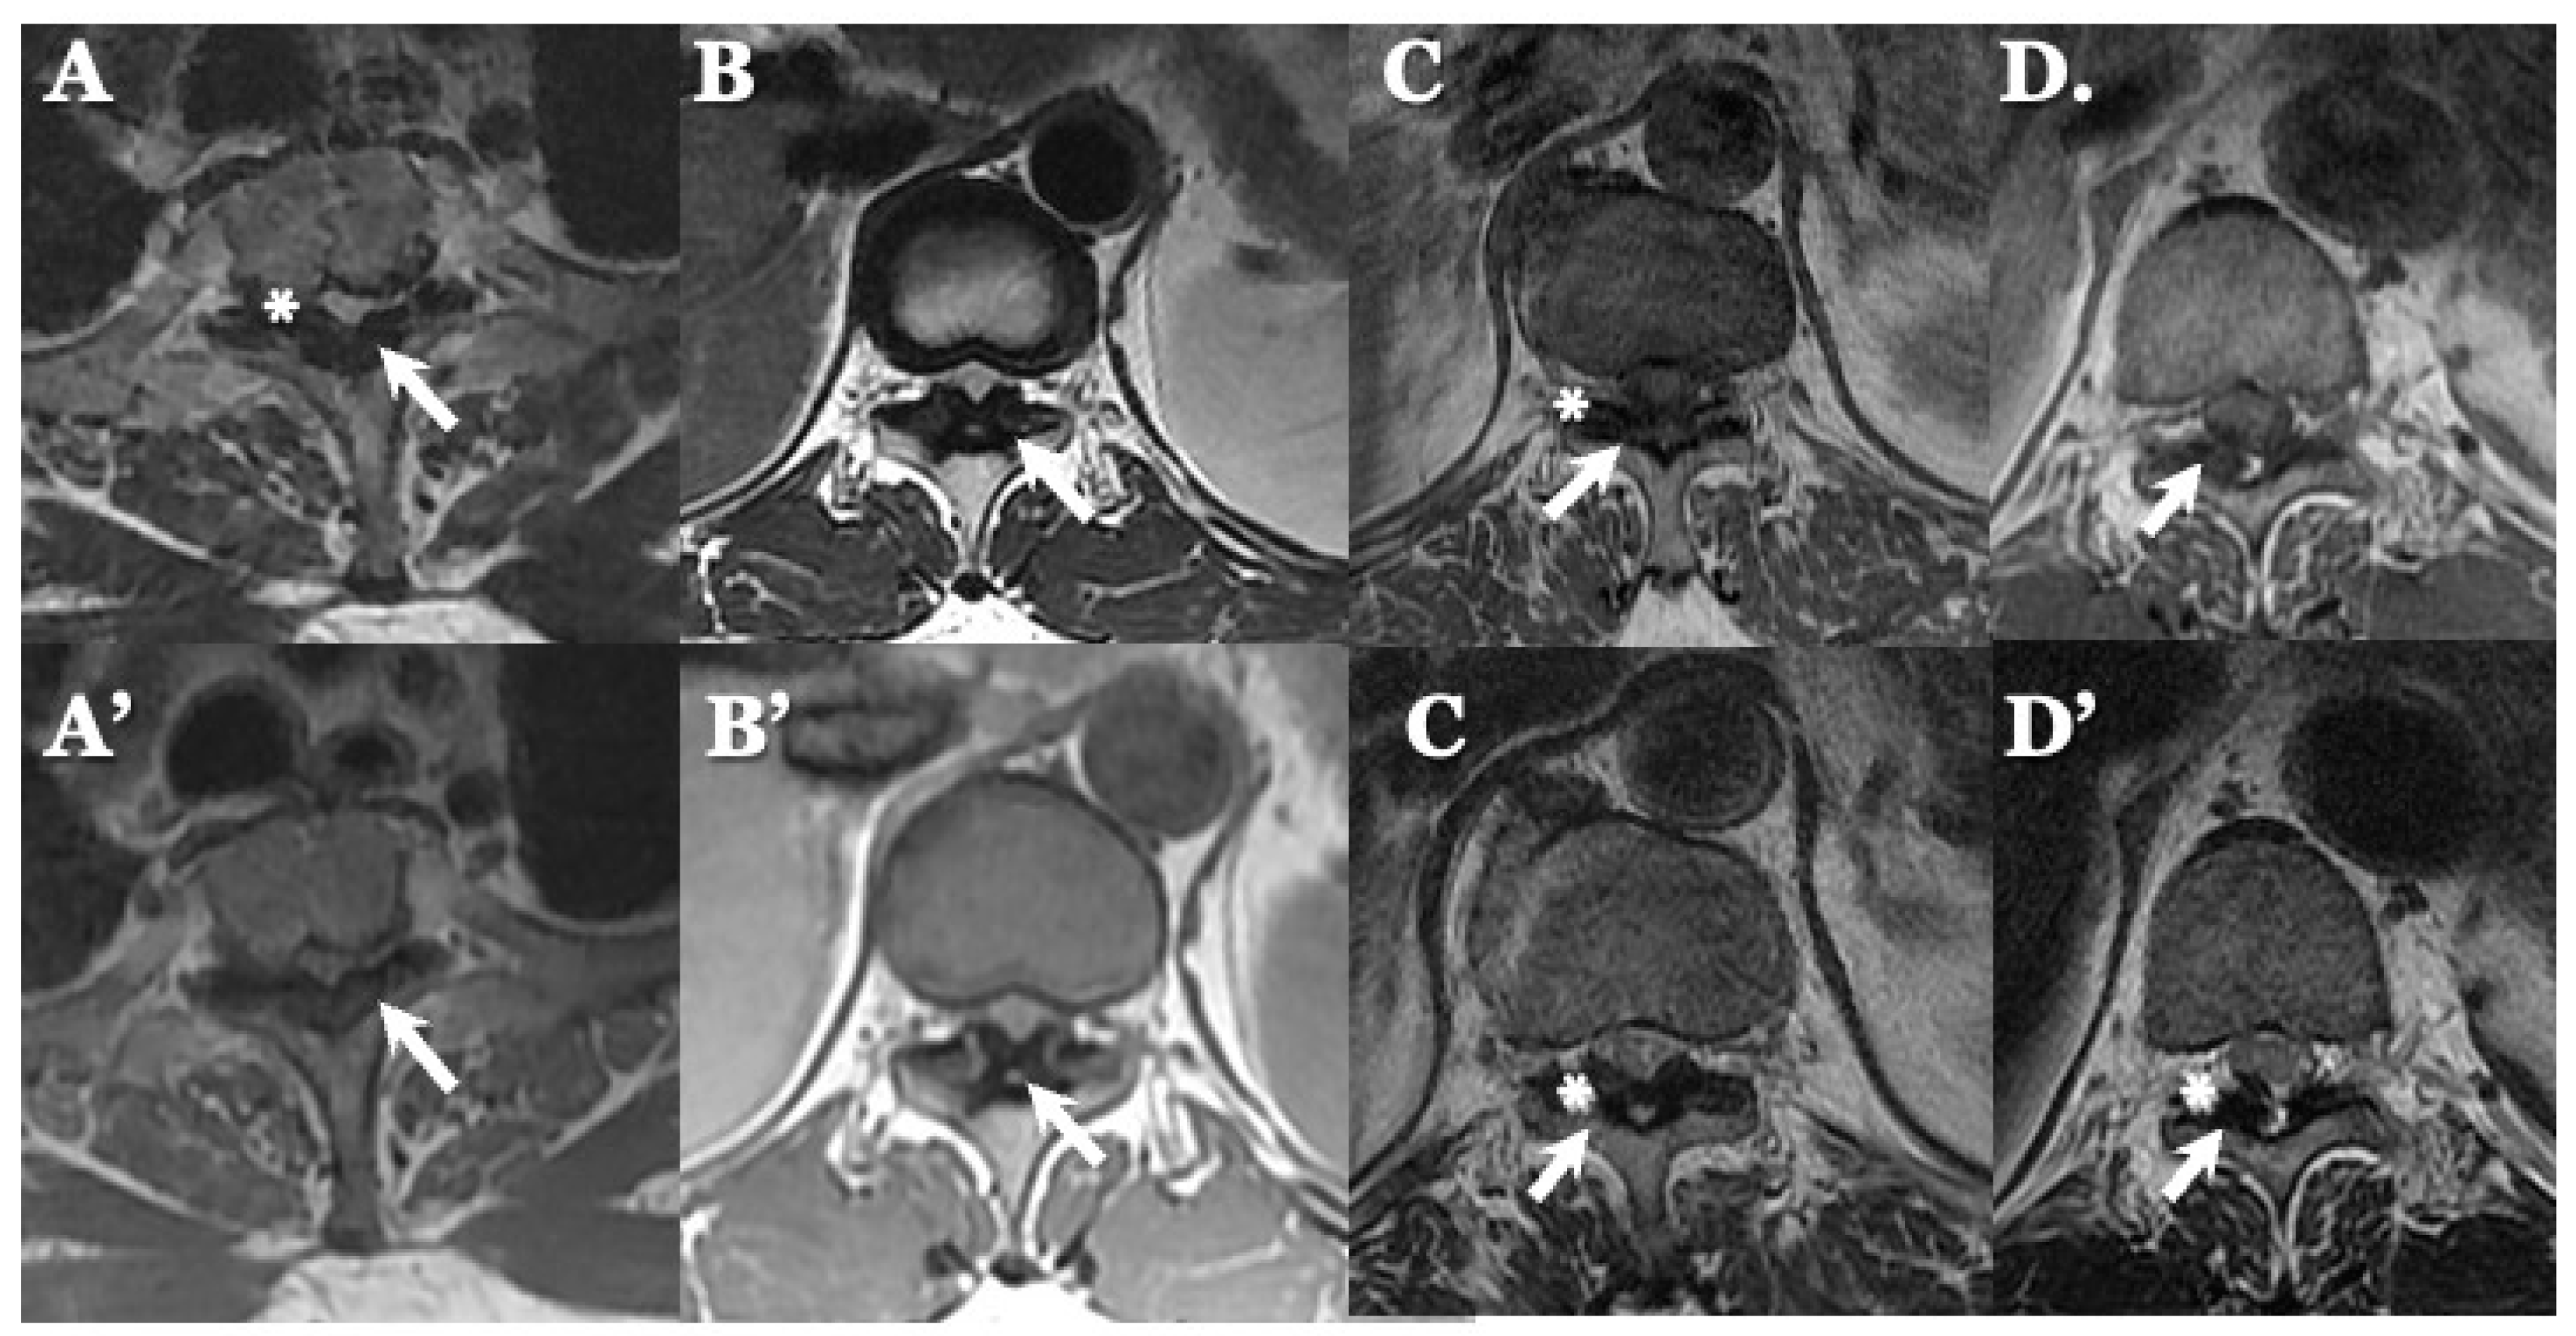

3.3. Neuroradiological Findings (Figure 3, Figure 4, Figure 5 and Figure 6; Table 3)

4.2. Comparison of Neuroradiological Findings between CLF and OLF (Figure 3, Figure 4, Figure 5 and Figure 6; Table 3)